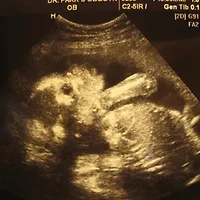

태아의 길이는 20cm이고, 몸무게는 400-450g입니다.

입술이 뚜렷해지고 눈과 눈썹, 속눈썹, 눈꺼풀이 선명해집니다.

아직 피하에 지방조직이 없어, 태아는 쭈글쭈글한 노인의 모습처럼 보입니다.